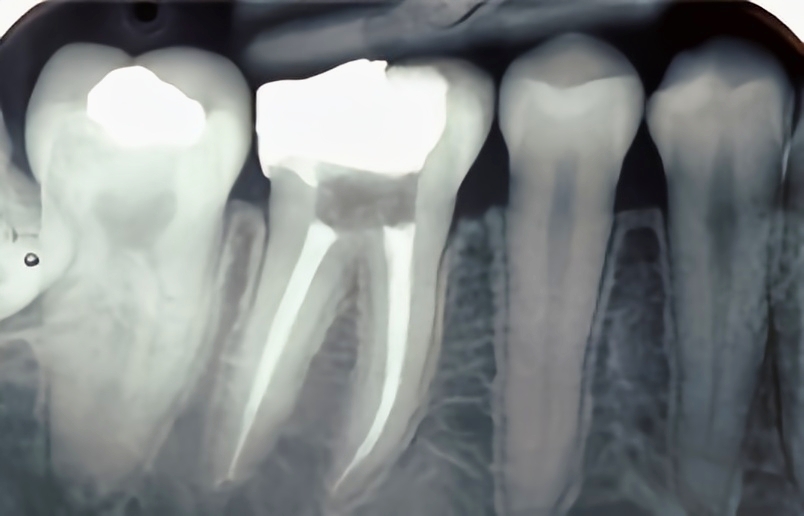

Save Your Tooth with Painless Root Canal Treatment...